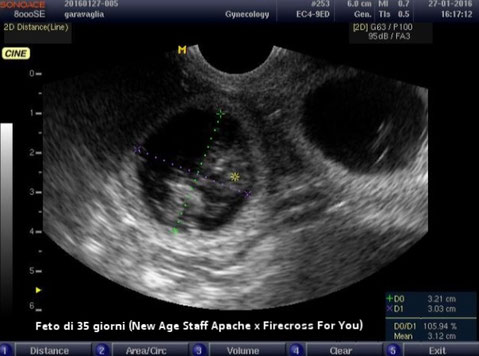

- Al 21° giorno dall'accoppiamento effettuiamo la prima ecografia per verificare la gravidanza in corso e la corretta maturazione degli impianti nei quali, successivamente, sarà ben visibile il feto. Questo primo controllo ecografico è molto utile per stabilire che non ci sia un riassorbimento fetale in corso;

- Al 40° giorno dall'accoppiamento effettuiamo il secondo controllo ecografico per verificare la salute dei feti, il flusso cardiaco e le biometrie per stabilire la data del parto con una precisione di +1/-1 giorno;